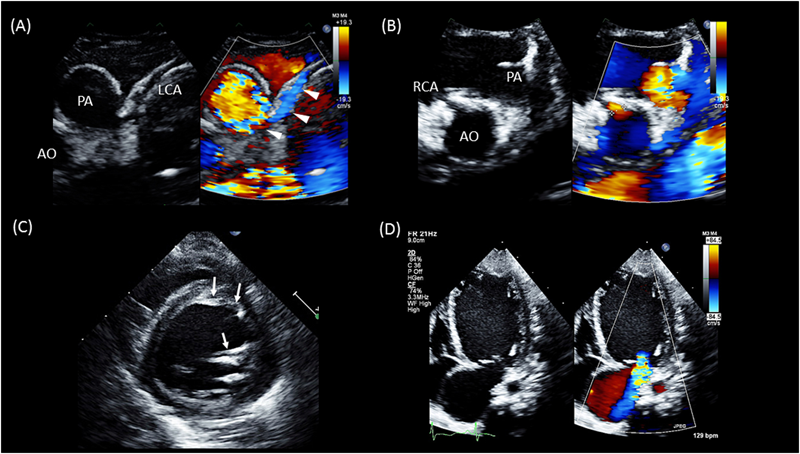

1886年にBrooksにより本疾患の最初の剖検報告が行われた53).その後1933年にBland, WhiteおよびGarlandらにより本疾患の系統だった報告が最初になされたことから,彼らの頭文字をとってBWG症候群とも呼ばれる54).本疾患の頻度は1/30万生産児と稀であり,また特殊な病態では学童期や成人期に発見される(成人型)こともあるが,ほとんどの症例は生後2~3カ月で発症する(乳児型)55).初発症状が重度の循環不全によるショックのことが多くあり,大動脈弁狭窄や大動脈縮窄等を除外した上で拡張型心筋症との鑑別が重要になる.心エコーによる左冠動脈血流の描出が非常に重要になるが,左冠動脈の肺動脈還流部は症例によっては確認困難なことがある.しかし,末梢左冠動脈は比較的容易に描出でき,カラードプラのスケールを下げることにより冠動脈内の血流を確認し,拡張期もしくは連続性の逆行性血流を確認できるようであれば診断は確定的となる(Fig. 6).左冠動脈還流領域の虚血性変化,特に左前乳頭筋のエコー輝度上昇や前中隔から左室前壁の心内膜エコー輝度上昇なども支持所見として有用である.また,心拡大と乳頭筋機能不全に伴った重度の僧帽弁閉鎖不全を合併する(Fig. 6).右冠動脈の拡大も支持所見として有用であるとされるが,この所見は側副血管の発達が未熟な乳児期早期には顕著でないことが多い.左冠動脈の肺動脈への開口部は肺動脈背側(facing sinus)が多いが,前肺動脈洞や左右肺動脈分岐部等の大動脈基部から離れた場所へ還流する場合もあり,還流部位の診断は手術法の選択の上で術前情報として必要である56).エコーでの診断が不可能な場合には造影検査を行う.なお,成人型おいては,左冠動脈の肺動脈還流部に狭窄が存在し,肺動脈へのcoronary stealが起こりにくい血行動態に加えて,右冠動脈から左冠動脈灌流領域への側副血行路が非常に発達していることが多い.また,ほとんどのALCAPA症例は単独の心疾患であることが多いが,動脈管開存症等の短絡性心疾患を合併することにより肺高血圧が維持されている場合や末梢性肺動脈狭窄により主肺動脈圧が高圧に維持されている場合などもcoronary stealを軽減し症状が緩和されていることがある.これらの症例では合併心奇形の治療後に急速に心筋虚血が進行しALCAPAの症状が出現することがある.治療については,乳児型においては診断が確定次第,全例速やかに手術介入を行う必要がある.一方,成人型においても突然死の発生率が8割を越えることから,たとえ無症状で虚血所見を欠く症例に対しても手術介入を行うことが推奨されている2).手術には左冠動脈の大動脈への移植やTakeuchi法等が知られているが,詳細については他章に譲る.なお,合併する僧帽弁閉鎖不全に対して僧帽弁の形成術を同時に行うかどうかについては未だ統一された見解はない.

Fig. 6 Anomalous left coronary artery from the pulmonary artery (ALCAPA)

(A): Left coronary artery: Note the retrograde flow in the left coronary artery (white arrowheads) that drains into the posterior aspect of the pulmonary artery.(B): Right coronary artery at the normal position of the right aortic sinus with antegrade flow.(C): Short axis view of the left ventricle: Note the increased brightness of the endocardium of the anteroseptum and anterolateral papillary muscle (arrow).(D): Apical chamber view displays moderate mitral regurgitation.AO: aorta; LCA: left coronary artery; PA: pulmonary artery; RCA: right coronary artery.